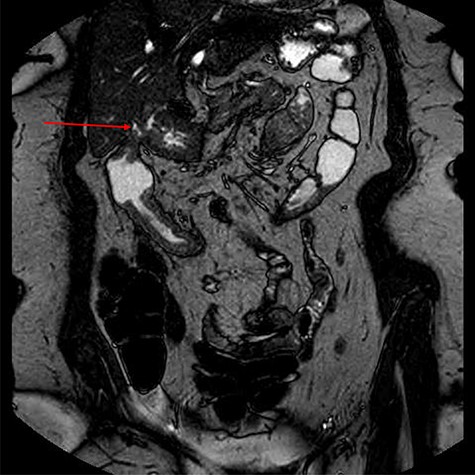

Computed tomography (CT) revealed a complex fistulous communication between the distal stomach and biliary tree with associated pneumobilia, and between the transverse colon and the distal stomach (Fig. 1). No gallstones were seen. Upper and lower gastrointestinal endoscopy was performed, revealing a prepyloric gastric ulceration and fistula (Fig. 2), with no obvious gastric pathology, which extended into the colon and a blind end structure assumed to be the gallbladder. Colonoscopy demonstrated an area of slight narrowing from the hepatic flexure to mid-transverse colon, with macroscopic colitis (Fig. 3). Biopsies were non-specific, with IBD a possibility, but the features were not pathognomonic.

CT abdomen and pelvis demonstrating fistulous communication between distal stomach and transverse colon (red arrow) with pneumobilia.